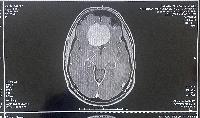

On October 16, 2023, I got the results of an MRI that showed a large mass consistent with a meningioma, a type of tumor of the meninges, which is the tissue separating the skull and the brain.

MRI, top view